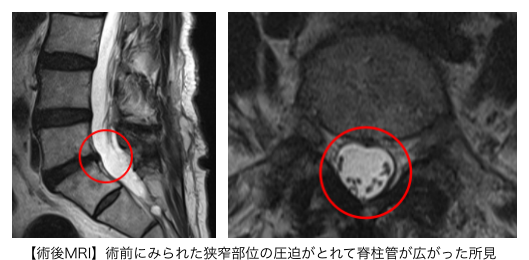

腰椎MRIからL5/Sの狭窄が症状の原因と判断し、PEL(脊柱管狭窄症内視鏡下手術)を実施。神経修復の効果を期待して、同時にPRP療法(濃縮血小板由来の成長因子を投与する再生医療)も行いました。

手術前の痺れを10とすると、術後2日で6まで軽減しました。術後半年以上経過して痛みも軽減しており、歩行距離も伸びました。